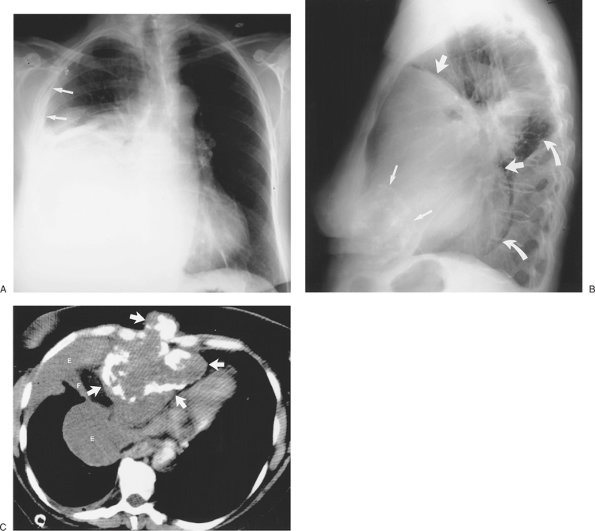

FIGURE 9-7. Pulmonary edema and pleural fluid pseudotumor. A: PA chest radiograph shows enlargement of the cardiac silhouette, interstitial pulmonary edema, and displacement of the inferolateral lungs from the chest wall and diaphragm by pleural effusion (straight arrows). There is a hazy "mass" in the left middle and lower hemithorax (curved arrows). B: Lateral chest radiograph shows that the "mass" or "pseudotumor" (curved arrows) blends in with the left major fissure (straight arrows); this is characteristic of pleural fluid within the fissure. The superior aspect of the left major fissure is thickened as a result of pleural fluid and subpleural edema (arrowheads).

FIGURE 9-8. Pleural fluid pseudotumor. A: PA chest radiograph shows a circumscribed ovoid mass in the right lower hemithorax (solid arrows) and thickening of the minor fissure (dashed arrow). B: Lateral view shows that the mass (arrows) is oriented in the direction of and superimposed on the major fissure. C: CT (bone windowing) shows that the mass is of fluid attenuation, representing pleural effusion (E), and is contiguous with the thickened major fissure (arrow).